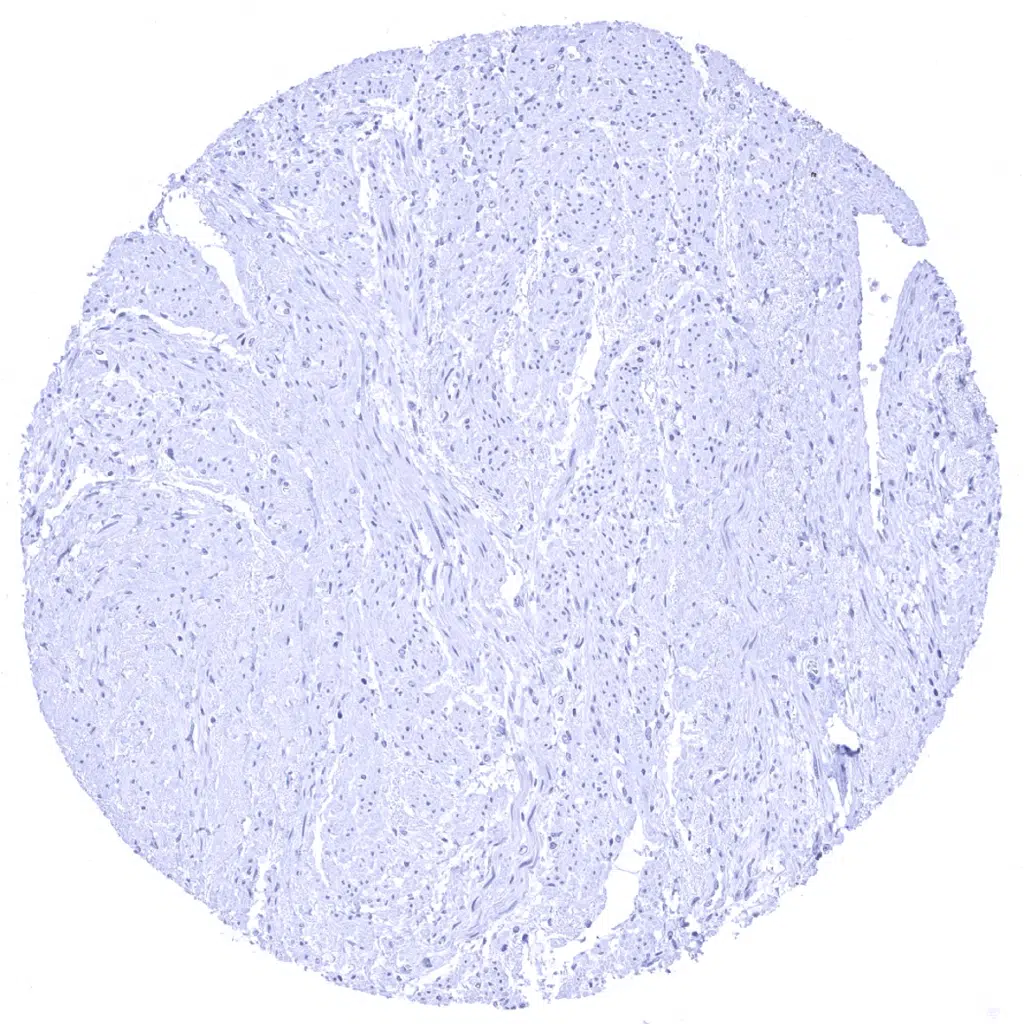

Thymus - Cytokeratin 13 immunostaining is seen in a fraction of thymic epithelial cells.

Thymus - Cytokeratin 13 positivity is seen in a fraction of thymic epithelial cells.